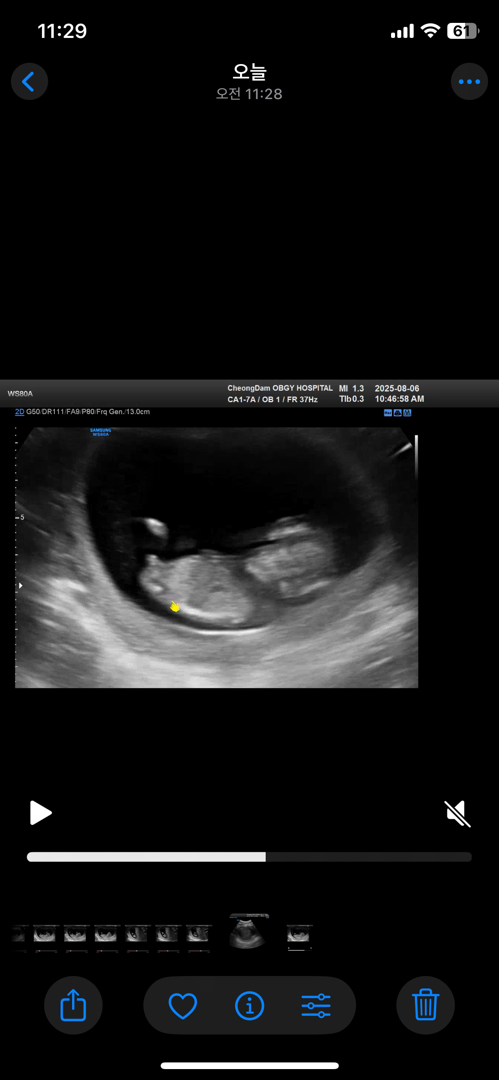

11주3일차 각도법봐주세요 !

다리사이에는 모가보인다는데 ㅠㅠ 각도법은 뭐같나요!!!

엇 근데 각도법상으로 아들 같아요!

저 시기에는 아들 딸 다 튀어나와있대요~